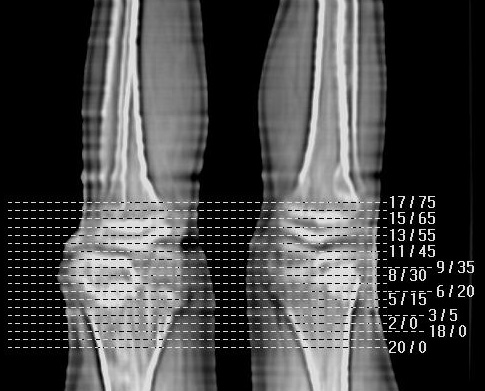

标题: PED0940:M12Y,左股骨下端酸痛畸形 [打印本页]

标题: PED0940:M12Y,左股骨下端酸痛畸形

12岁男孩,左膝关节肿痛8年,近月明显